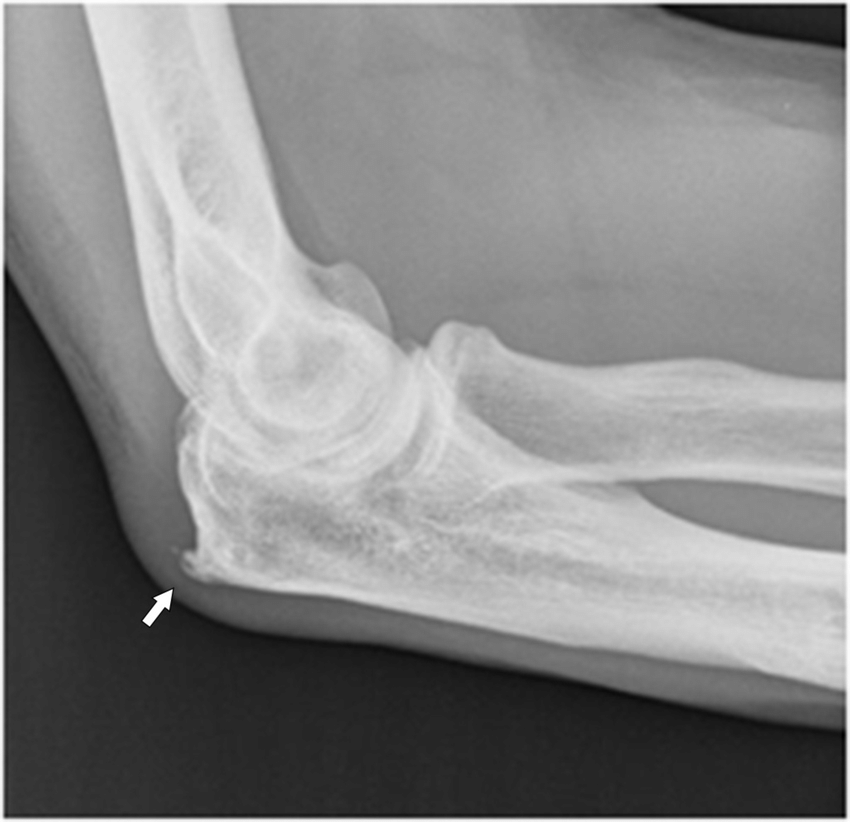

1. ตรวจเอกซเรย์ เพื่อหาดูสิ่งแปลกปลอมหรือกระดูกงอก ในคนไข้บางคนที่มีถุงน้ำอักเสบบ่อยๆอาจพบกระดูกงอกที่กระดูกปลายศอก

รูปภาพ : กระดูกงอกที่กระดูกปลายศอก ( แหล่งที่มาของภาพ : https://www.researchgate.net/figure/Plain-films-showing-spur-formation-arrow-at-the-olecranon-References-Department-of_fig20_280001741 )